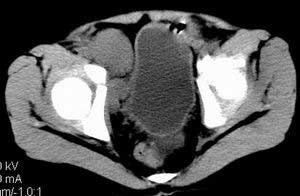

| 患者,男,9岁,因右下腹包块入院,血象不高,不规则发热,常超40度。 平扫: ![]() ![]() ![]() ![]() ![]() ![]() ![]() ![]() ![]() ![]() ![]() ![]() ![]() ![]() ![]() ![]() ![]() ![]() 增强: ![]() ![]() ![]() ![]() ![]() ![]() ![]() ![]() ![]() ![]() ![]() ![]() ![]() ![]() jiajie发言:骶椎右前区不规则软组织肿块,边缘光整,密度均匀,增强后均匀强化,右腹股沟区可见肿大淋巴结,临床有时发热,考虑淋巴瘤,儿童盆腔肿瘤应与神经母细胞瘤和横纹肌肉瘤鉴别。 longzhanghui发言:印象:盆腔右后壁不规则软组织肿块,并向前延伸.似为多个肿块融合,呈中等强化.初步考虑淋巴瘤. 听蝉观竹发言:右侧髂内、外组淋巴结肿大,从其形态和融合的情况看,同意大家意见-----考虑恶性病变,但是9岁男孩还要注意检查睾丸情况,有无隐睾? 常常类似情况是隐睾发生精原细胞瘤淋巴结转移,这个病例也要注意这一点!!! 广东凌发言:大家好,在这里我想说一下个人观点,我建议上传图片的同志能否辛苦一点就是把病史和图片都上传完整一点,比如这个病人的腹膜窗,并且这个病人的肠道的准备也是不怎么好,就从现有的质料看:病灶属于淋巴结肿大当无大的争议,有融合趋势,其内无坏死,边缘强化为主,故考虑:淋巴瘤!建议用腹膜窗看一下和肠道的关系! 阿圣发言:病灶属于淋巴结肿大当无大的争议,有融合趋势,其内无坏死,边缘强化为主,故考虑:淋巴瘤 结果是:淋巴瘤 病例来源:ct762。由宁静致远发布: http://www.radinet.com.cn/forum_view.asp?forum_id=4&view_id=2182 |